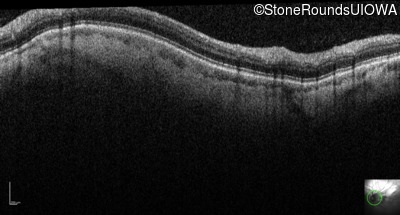

Infrared Fundus Photograph - Left - 20/100

Exemplar